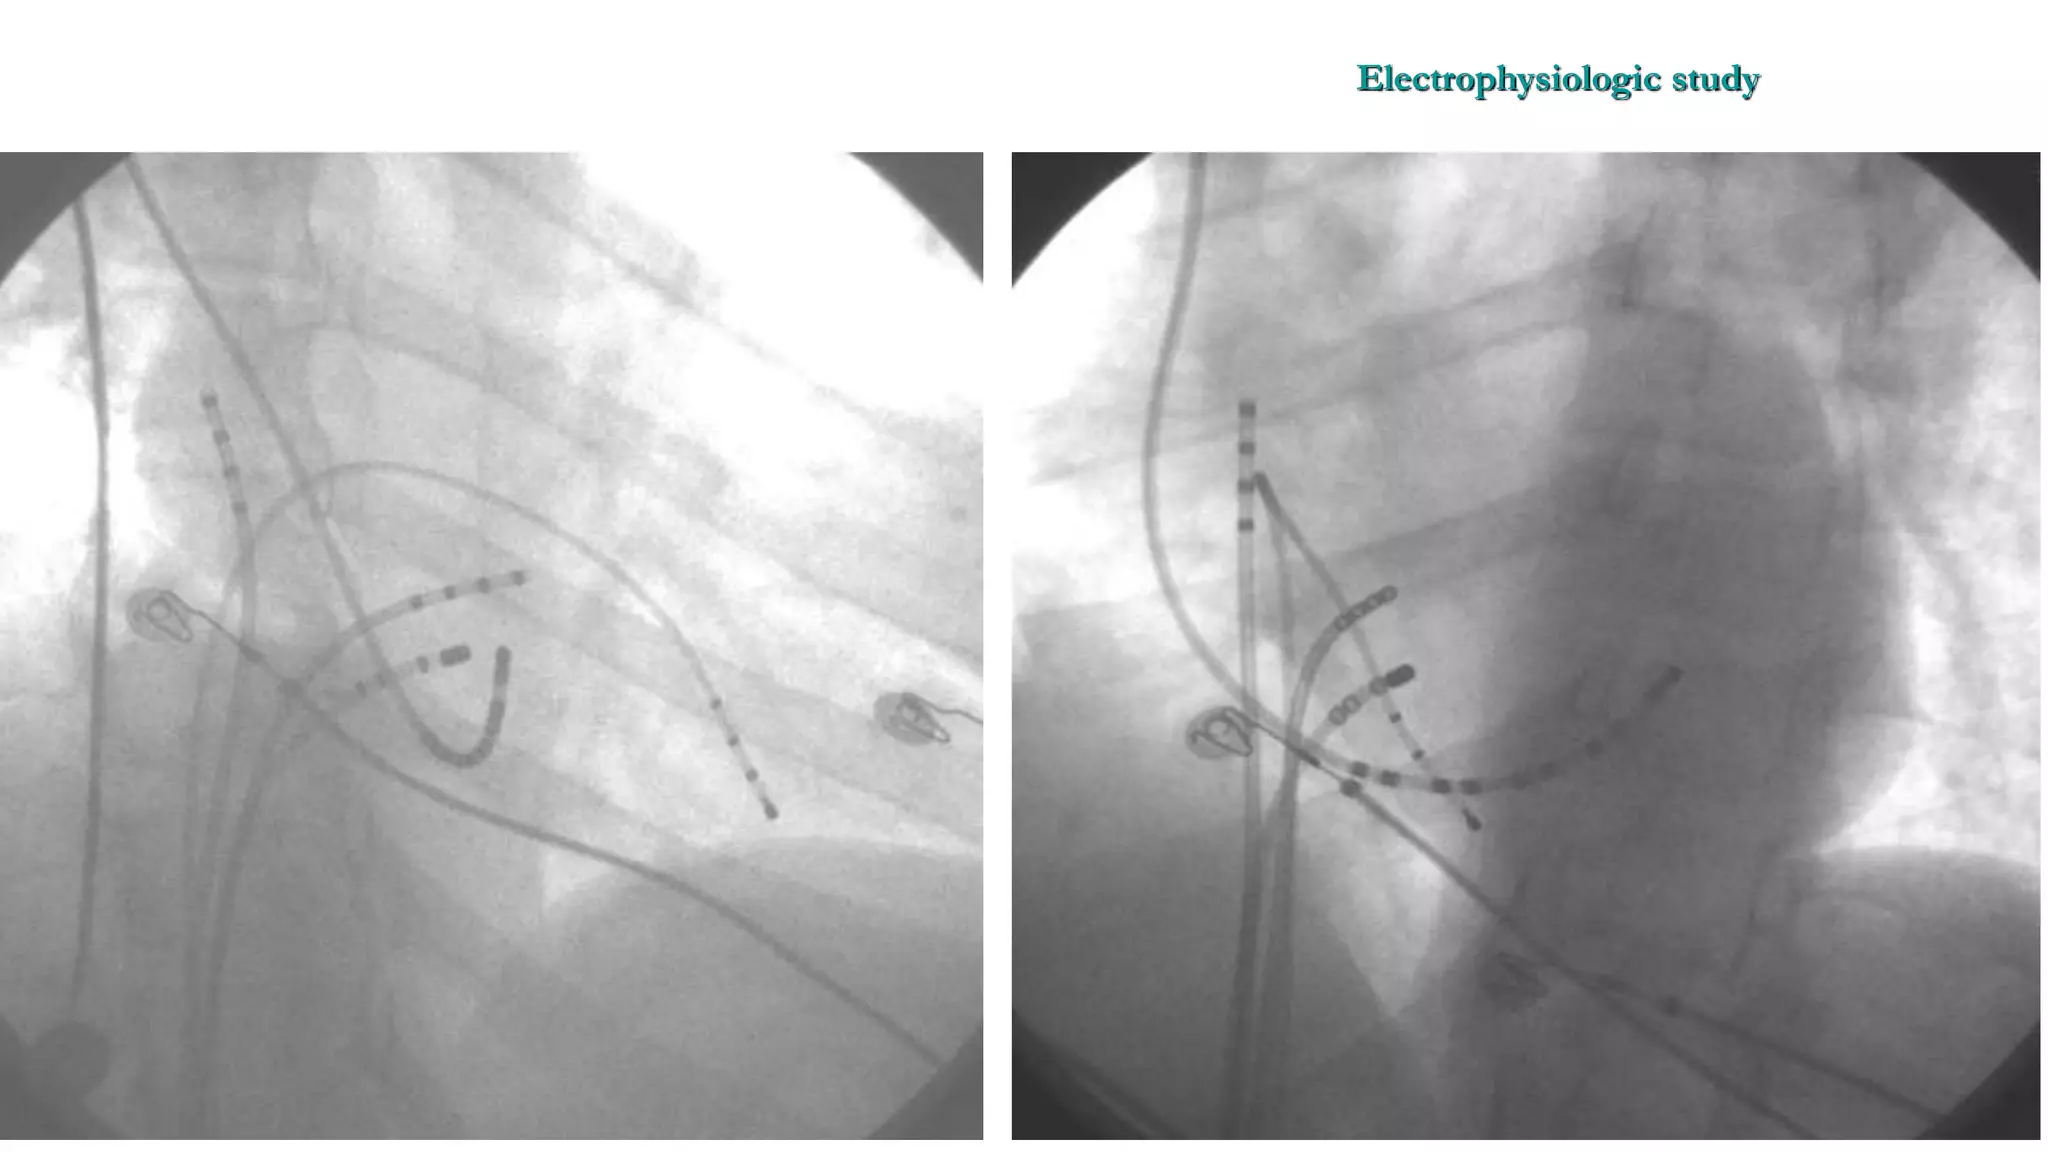

An electrophysiologic study involves inserting electrode catheters into the heart to record electrical activity and induce arrhythmias. The document discusses: 1. The procedure involves placing catheters in the heart to record electrograms from the atria, His bundle, ventricles and coronary sinus. 2. The aims are diagnostic to evaluate arrhythmias and bradycardias, and therapeutic for ablation of arrhythmias. 3. Key measurements taken include intervals between P waves, His bundle activation and QRS complex to identify conduction abnormalities. 4. Tracings are analyzed to determine the rhythm, sequence of activation, effects of pacing, and identify arrhythmia mechanisms like accessory pathways